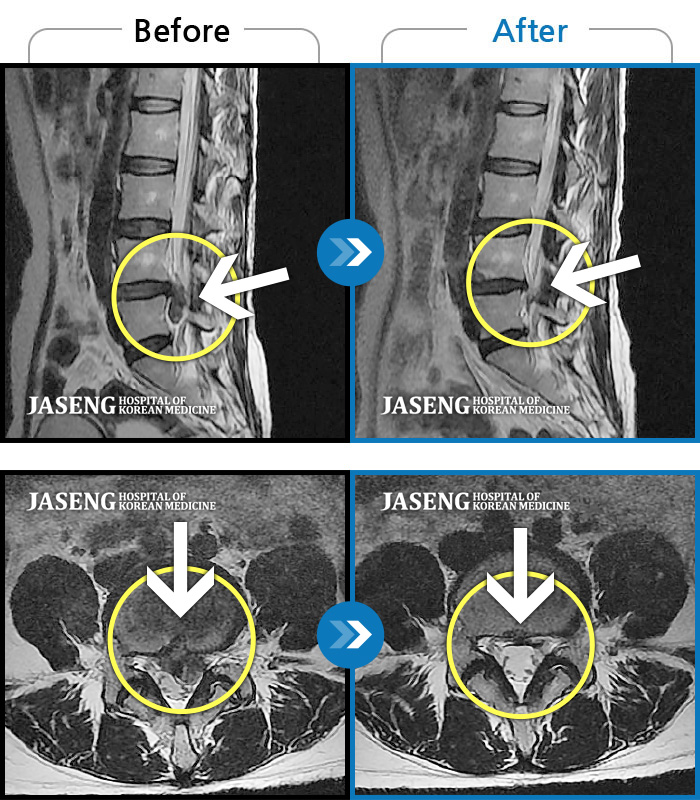

허리디스크

일산 · 배영현 교육수련부장

허리, 좌측 골반부터 좌측 다리로 통증 및 저림이 지속되고 좌측 다리의 감각이 둔함

촬영시기

2024.09.30 ~ 2025.11.25

2025.12.05